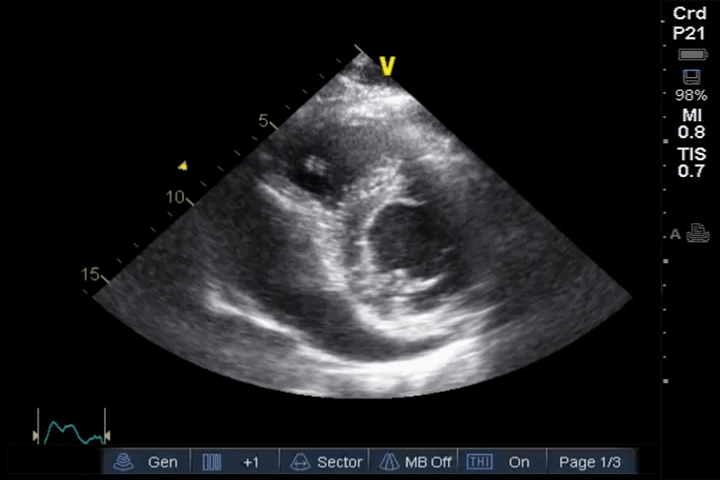

PLAX

PSAX view showing large pericardial effusion with compromised cardiac filling: This PSAX view shows a massive pericardial effusion, with the heart appearing to float and pendle within a large fluid collection. The fluid volume is almost three times the size of the heart, and the filling of the heart is severely compromised due to the pressure exerted by the surrounding fluid. These findings are indicative of a large effusion with a high risk of tamponade.